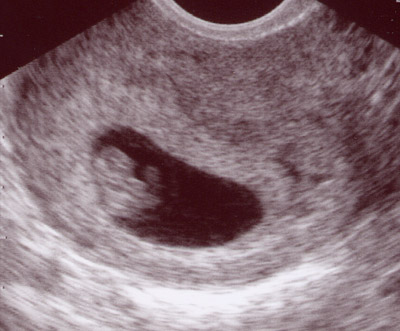

I went to the doctor today for a routine checkup on the baby. It was my first time to meet the doctor, and after asking my huge list of questions and getting answer after answer that impressed me, I must say I really like him a lot. My questions included everything from heart defects, to intervention during labor, to postpartum depression. I found out they are able to do the type of ultrasound to check for heart defects we need here in Springdale, but I still requested to go down to Little Rock, as I am comfortable with the doctors there. So that is in the works to be scheduled, my guess is it will be sometime in March. After talking with him for about 30 minutes he did a quick ultrasound to just peak at the baby and it is amazing how much they grow in just 4 weeks. I'll show you this morning's ultrasound next to the one from a month ago and you can see how much has changed.